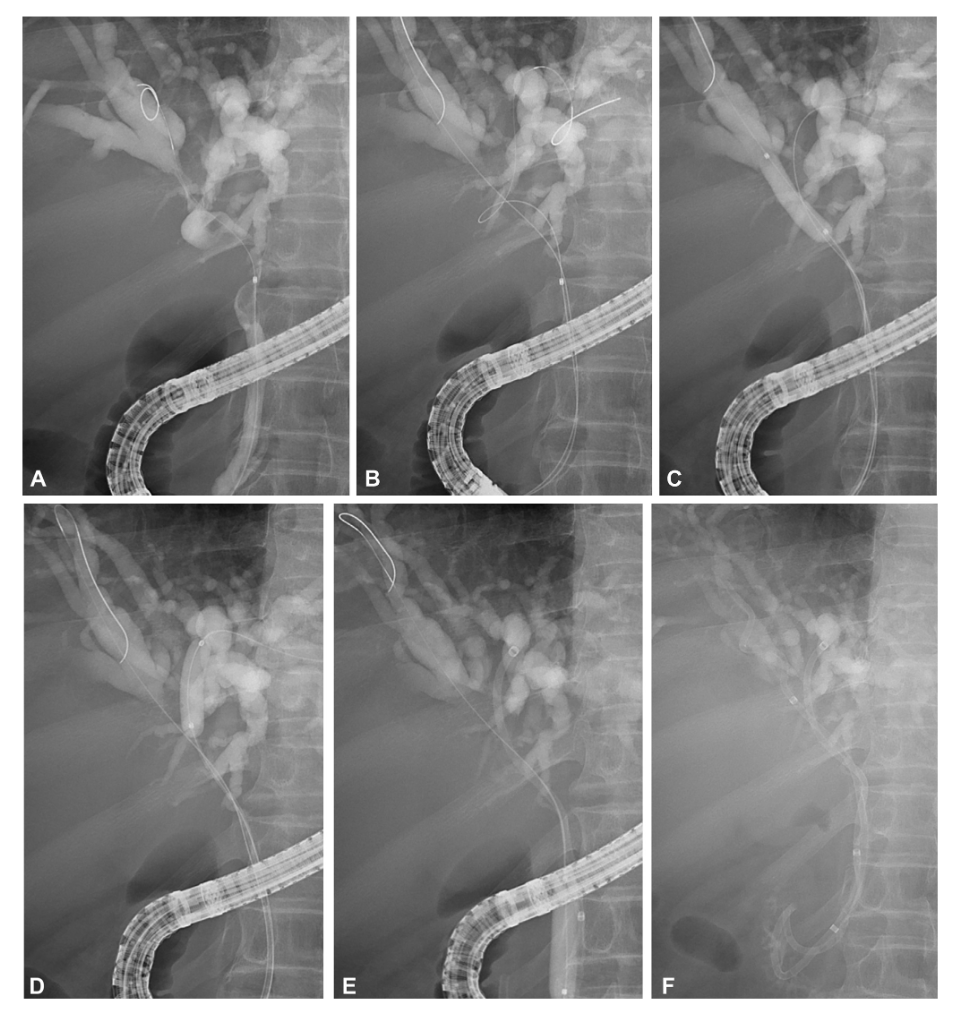

研究结果提示,技术和临床成功率分别为96.9%和84.4%。53.1%(17/32)的病例进行了双侧支架置入,所有病例的技术成功率均为100%。3个月支架通畅率为76.9%,支架通畅的中位持续时间为146.0天(95% CI,122.7-169.3天)。在225.0天的中位随访期内,未观察到自发性支架移位病例。胆泥形成是晚期支架功能障碍的最常见原因,发生在28.1%的患者中。图2为一列ERCP的内镜操作示例。

图片51.png

图2  内镜下放置扭转塑料支架治疗肝门胆管梗阻。A.内镜逆行胰胆管造影图像显示恶性肝门梗阻患者使用导丝选择性插管右IHD。B.使用第二导丝选择性插管左侧IHD。C.内镜下球囊扩张右主干IHD狭窄,便于支架置入。D.内镜下球囊扩张左主干IHD狭窄,以确保足够的管腔扩张。E.将第一个扭转塑料支架部署到左侧IHD中。F.双侧支架置入成功,两个扭转塑料支架并排放置。